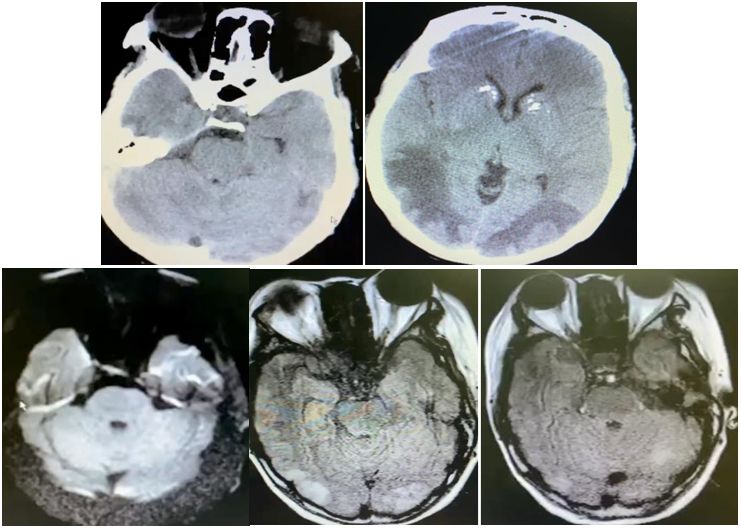

66岁女性,头痛原因待查。

答案:颅底脊索瘤(chordoma)。脊索瘤是一种罕见的缓慢生长的恶性骨肿瘤,通常发生在脊柱或颅底。来源于残存的脊索组织,具有肉瘤的部分特点。通常在40-70岁发病。男性多于女性。脊索瘤可以发生在脊柱和颅底的任何部位。CT一般表现为溶骨性骨质破坏,常伴有膨胀性软组织肿块,内有散在斑片状钙化,少数边缘表现为骨质硬化。MRI信号呈长T1、长T2信号,信号不均匀,增强后多呈中度至明显不均匀“蜂窝”状强化。矢状位桥脑腹侧呈“指压状”凹陷。要和垂体瘤、脑膜瘤相鉴别。治疗包括外科手术、放疗和靶向治疗等。